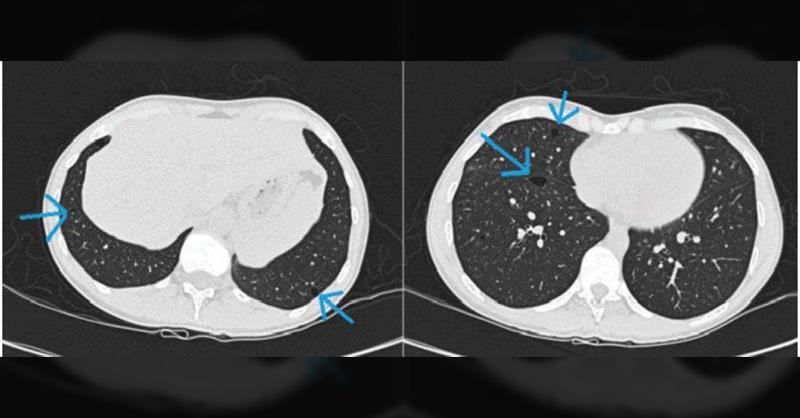

A 29-year-old female presented with a spontaneous pneumothorax (SP) 2 days after completing a half marathon. The SP was treated successfully with drainage. Further, a high-resolution computed tomography (HRCT) scan was performed which showed multiple cysts in the basal parts of the lungs. To further investigate, pulmonary function tests and magneti